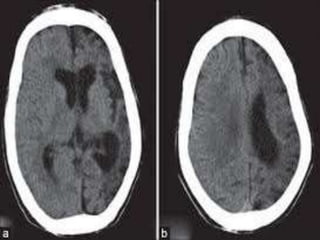

Venous infarct

Vascular Insults • SubarachniodHemorrhage. • Lobar and basal ganglia bleeds. • Ischemic strokes. • Venous infarcts. • Disections